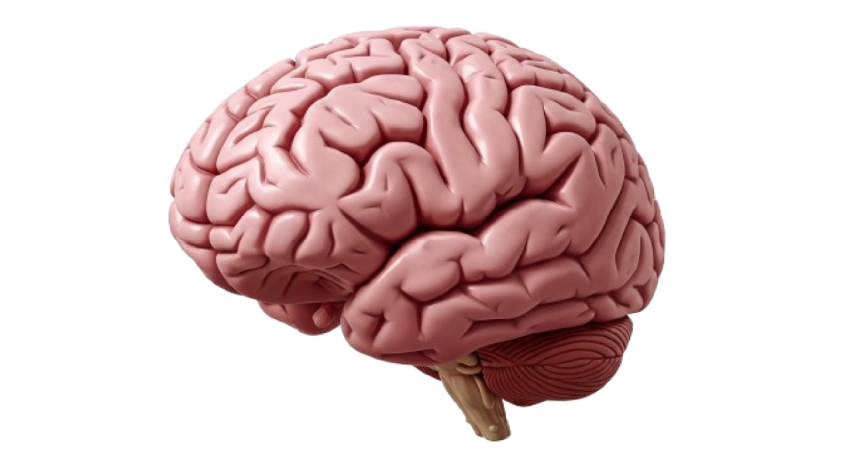

Detailed 3d rendering of the human brain with cerebellum and brainstem

human brain anatomy cerebrum cerebellum brainstem neurology medical illustration science biology organ central nervous system lobes gyri sulci model 3d rendering realistic health cognition mind thinking learning memory function neuroscienceSimilar Photos

- Photo type PNG

- Resolution 2668x1454

- Category Health / Medical

- File size 278.7kB